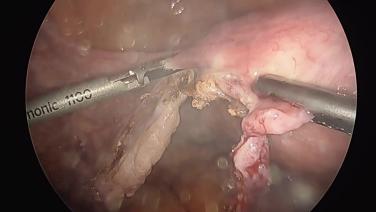

Total Laparoscopic Hysterectomy - Divide Broad Ligament

Total Laparoscopic Hysterectomy - Transect Utero-Ovarian Ligaments

Total Laparoscopic Hysterectomy - Ligate & Divide Mesosalpinx

Total Laparoscopic Hysterectomy - Ligate & Divide Round Ligaments

Total Laparoscopic Hysterectomy - Adhesiolysis